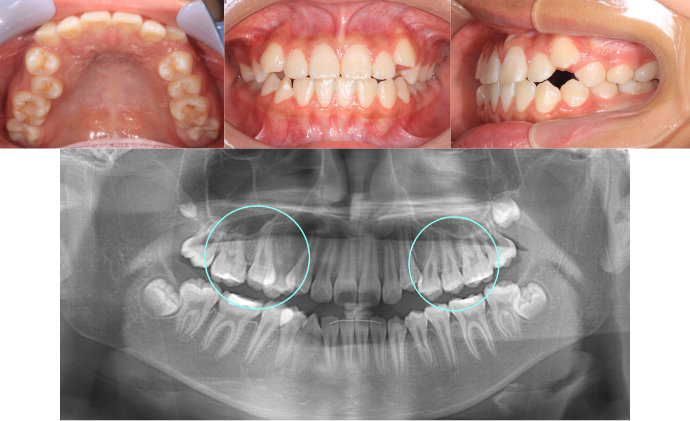

| Case1 |

| 出っ歯 |

| <治療前> |

| <治療後> |

| 主訴 |

前歯が出ている |

| 診断名 |

上顎前突 |

| 年齢 |

8歳 |

| 使用装置 |

マルチブラケット装置 |

| 抜歯部位 |

永久歯の抜歯は無し |

| 治療期間 |

2年4か月 |

| 治療費概算 |

検査・診断料:5万円+税 装置・技術料:25万円+税 おおよそ1か月ごとの処置・管理料:5,000円+税 保定装置料:5万円+税 |

| リスク・副作用 |

う蝕 歯根吸収 |